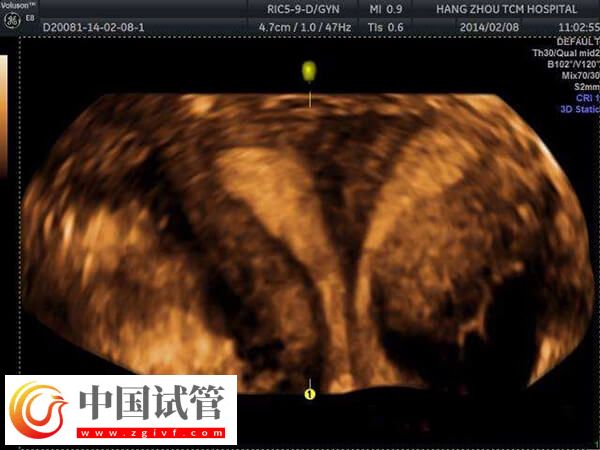

移植优胚出现的空囊的患者,可能是存在宫腔环境异常,如宫腔粘连、纵膈子宫等,会影响胚胎发育,导致妊娠空囊。这些情况通常需要通过宫腔镜下手术分离粘连或纵膈来改善。